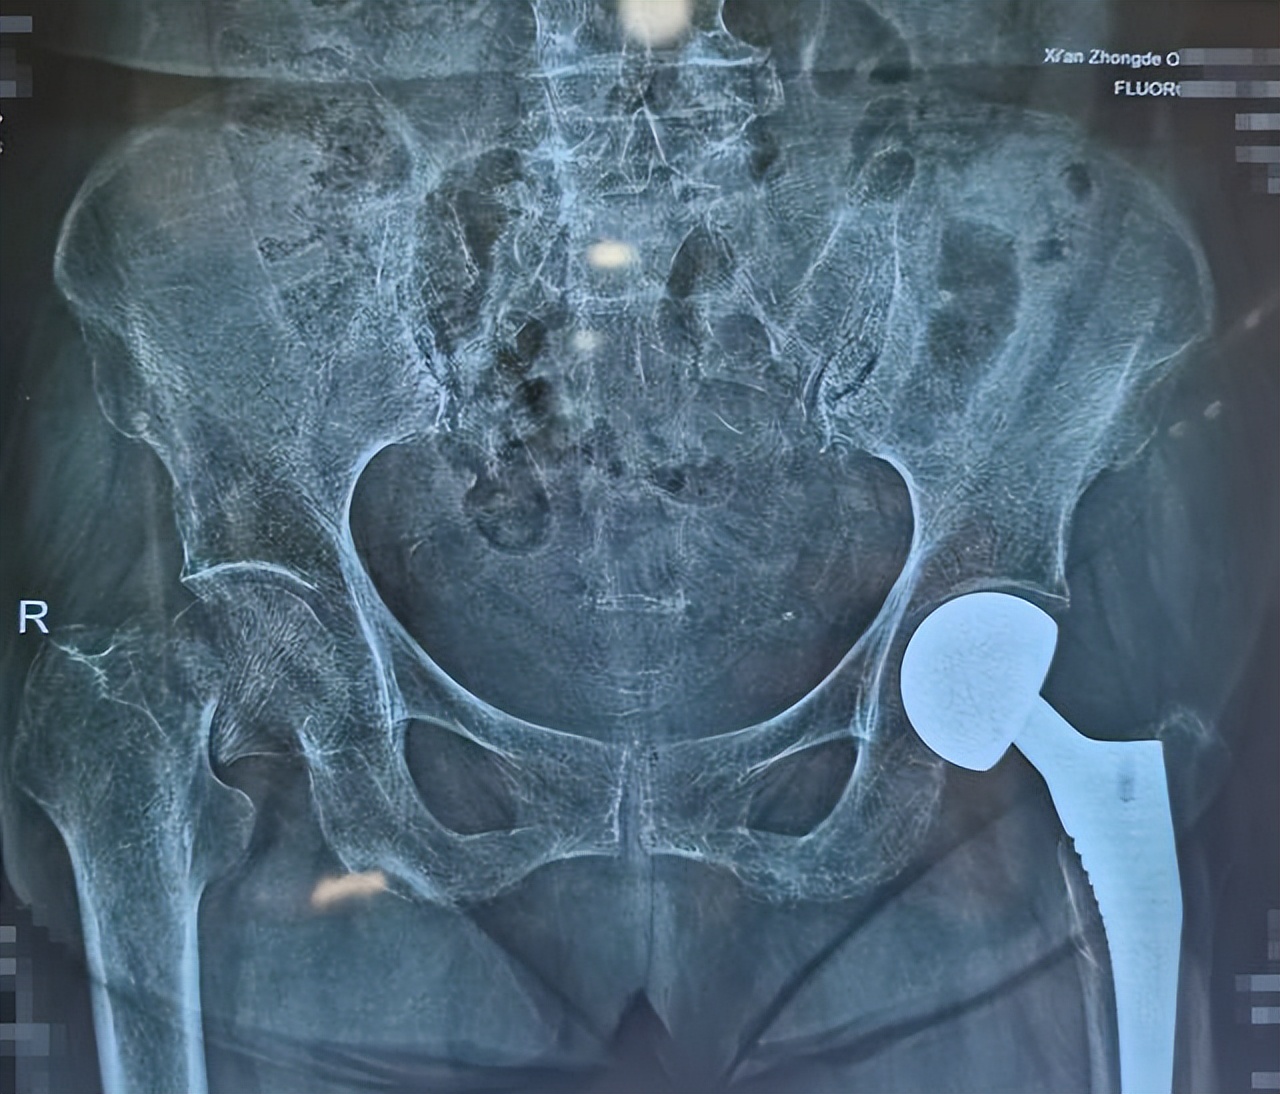

崔婆婆不慎跌倒,顿时感觉左髋部疼痛难忍,活动受限1天后住进医院。医生立即安排CT检查,诊断为左股骨颈骨折。

经检查,崔婆婆患有心功能不全、下肢动脉狭窄、贫血、低蛋白血症、重度骨质疏松等多种基础疾病,手术风险非常高。

经过严谨的评估与准备,由经验丰富的骨科主任、主任医师李程主刀,副主任医师邹杰和主治医师纪法源配合,凭借精湛的医术和默契的配合,仅用35分钟就完成了手术。为了最大限度保障患者的安全,骨科团队极致压缩手术时间,严格控制术中出血,大大降低了术后出现并发症的风险。这不仅是一次技术上的突破,更是对患者生命的尊重、对患者健康的珍视。